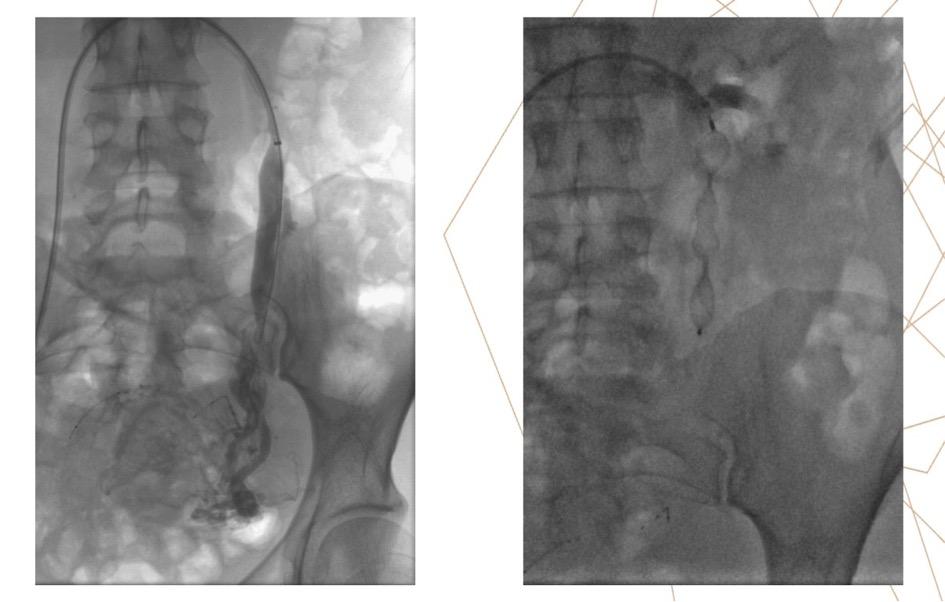

- 1er temps diagnostic : phlébographie iliaque interne, veine rénale, veine gonadique

- 2ème temps thérapeutique : embolisation (points de fuite veineux pelviens si ils existent et sont symptomatiques, varices pelviennes et veine gonadique gauche). Matériel d’embolisation variable (mousse sclérosante, colle biologique, coil…)

Figure 1 : phlébographie avant et après embolisation